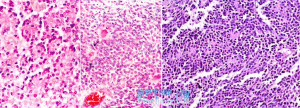

左圖:肥胖型星形膠質細胞瘤右圖:多形性膠質母細胞瘤本瘤約占顱內腫瘤的30%,占神經膠質瘤的80%以上。中年人最多,間變性星形膠質細胞瘤發病在50歲呈高峰,而多形性膠質母細胞瘤發病高峰晚10年左右。

肥胖型星形膠質細胞瘤(gemistocyticastrocytoma)主要含有肥胖型星形細胞,瘤細胞呈大的嗜伊紅細胞體,短鈍,成角的GFAP陽性的突起形成粗糙的纖維網架結構,胞核圓形,橢圓形,通常偏中心位。

膠質母細胞瘤(glioblastomamultiforme,GBM),腫瘤好發於額葉、顳葉白質,浸潤範圍廣,常可穿過胼胝體到對側,呈蝴蝶狀生長。瘤體常出血壞死而呈紅褐色。鏡下,細胞密集,異型性明顯,可見怪異單核或多核巨細胞。出現出血壞死,是其區別於間變性星形膠質細胞瘤的特徵。毛細血管內皮細胞增生,腫大,可導致管腔閉塞和血栓形成。本症預後差,患者多在2年內死亡。